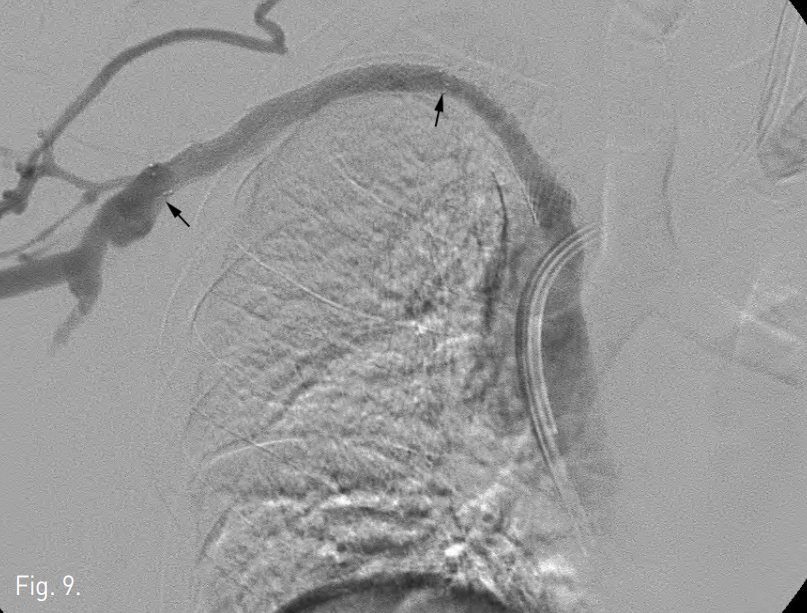

Fig. 8

A radiograph obtained during PTA using a 10 mm balloon catheter.

Fig. 9

Venogram obtained after PTA and subsequent stent placement (arrows) shows that full patency was reestablished.